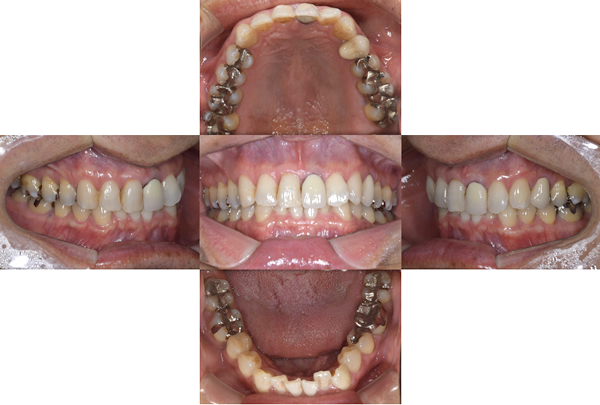

症例1

治療前

治療後

治療内容

口腔内の銀歯を全てセラミックにしたいというご希望でした。親知らずは抜歯しています。笑ったときや自然なスマイルをしたときも銀歯が見えなくなり自然になりました。

治療期間 約2ヶ月

治療費 合計:935,000円 (内訳)

オールセラミック:110,000円×5本

セラミックインレー:55,000円×7本

治療のリスク・副作用 銀歯の下で虫歯が大きくなっていたら歯の中の神経をとらないといけないことがあります。また、被せ物を外すと、ご自身の歯が少ない場合は別途はを残すための処置が必要になることがあります。